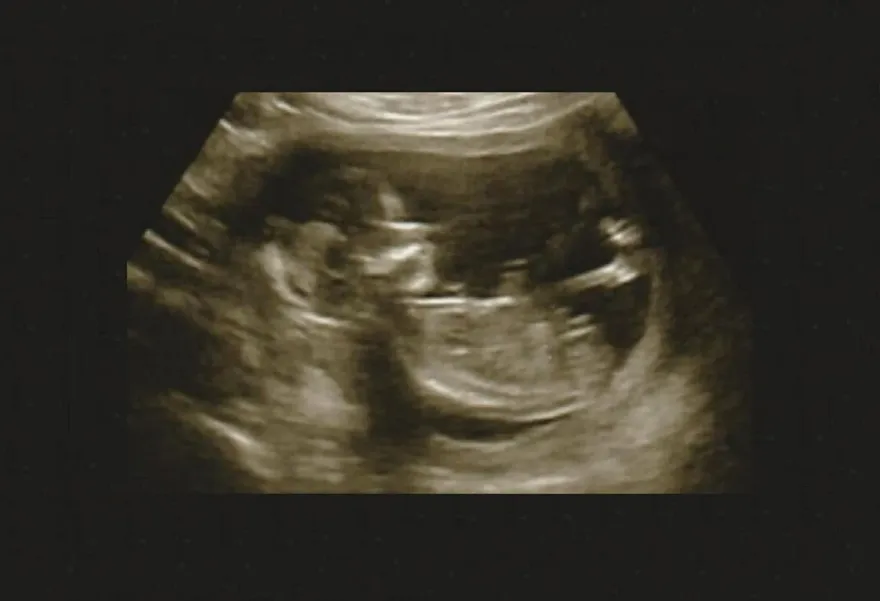

婦產科

蘇怡寧

超音波檢查

胎兒

心跳